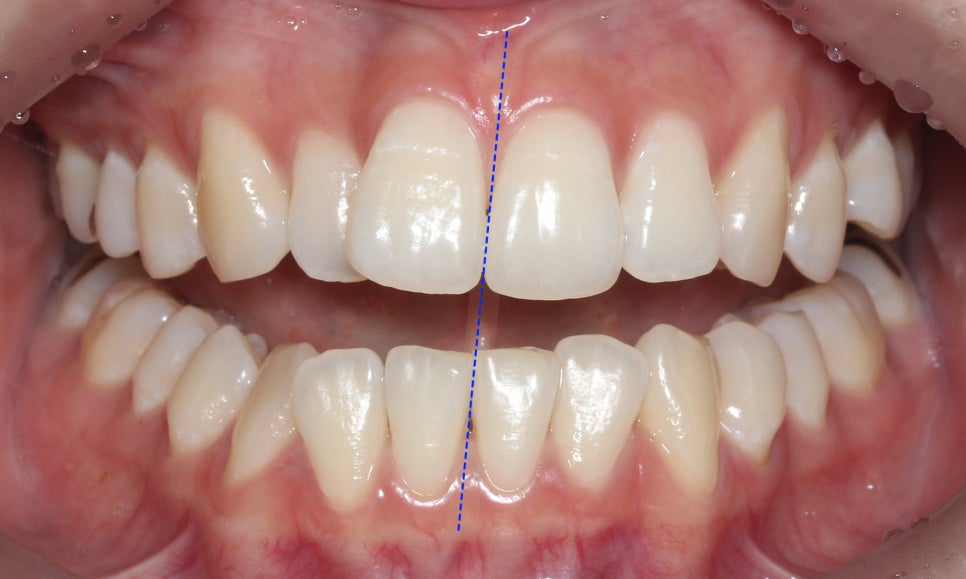

치아 개방 시 상악과 하악의 정중선을 보면

대각선으로 삐뚤어져 있는 것을 확인할 수 있는데요,

안모의 중심이 틀어져 있기 때문에 치아 개방-교합 시

한쪽으로 힘이 가중될 가능성이 있습니다.

교정 전 모습과 비교해보면 상하악의

중심이 바르게 잡힌 모습으로

거꾸로 교합되던 상악 측절치도

바르게 물리고 있는 것을 확인할 수 있습니다.